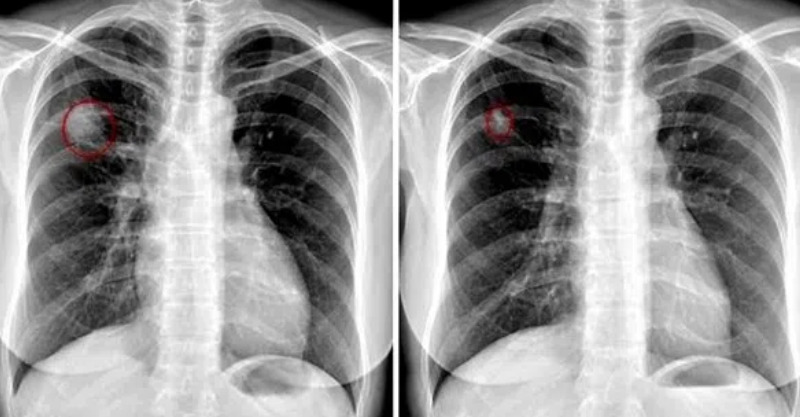

根據《三立新聞網》報導,一名65歲李姓婦人因長期手部麻痛困擾,接受腕隧道症候群手術治療,但症狀不僅未見好轉,反而逐漸出現呼吸困難及心跳不規則等問題。經過亞東醫院醫療團隊詳細檢查並進行基因檢測,最後確診為罕見的成人轉甲狀腺素蛋白類澱粉沈積症所引發的心肌病變。

亞東醫院心臟血管內科張藝耀主任表示,這類心臟病變是由不正常蛋白質在心臟肌肉堆積所造成,雖然無法完全痊癒,但及早發現並配合治療,仍可有效延緩惡化速度。他特別提醒,這種疾病有「三心兩異」的典型症狀,包括心律不整、心臟衰竭、心肌肥厚,以及神經系統異常和腎臟功能異常。

圖片來源:三九養生堂